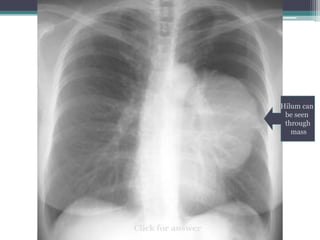

Hilum overlay sign

Can you see the pulmonary arteries on the

Hilum can

be seen

through

mass

โ€ข Answer: this must be an anterior mediastinal

mass because it overlaps rather than โ€œpushes

outโ€ the main pulmonary arteries

โ€ข This particular example is a thymoma